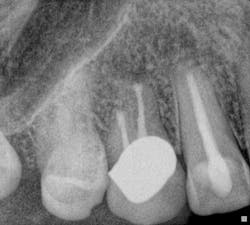

Fig. 8: Retreatment preop radiograph.Note the less-than-ideal technical status of the existing RCT with an incomplete coronal seal.

Fig. 9: Sinus tract tracing with GP.Endodontic treatment was necessary due to the persistence of a buccal sinus tract that can be traced to the radiographic apex of tooth No. 10, despite recent endodontic treatment. Retreatment was performed and the sinus tract persisted, despite the adherence to strict protocols for intracanal disinfection and establishment of a technically satisfactory intracanal seal.